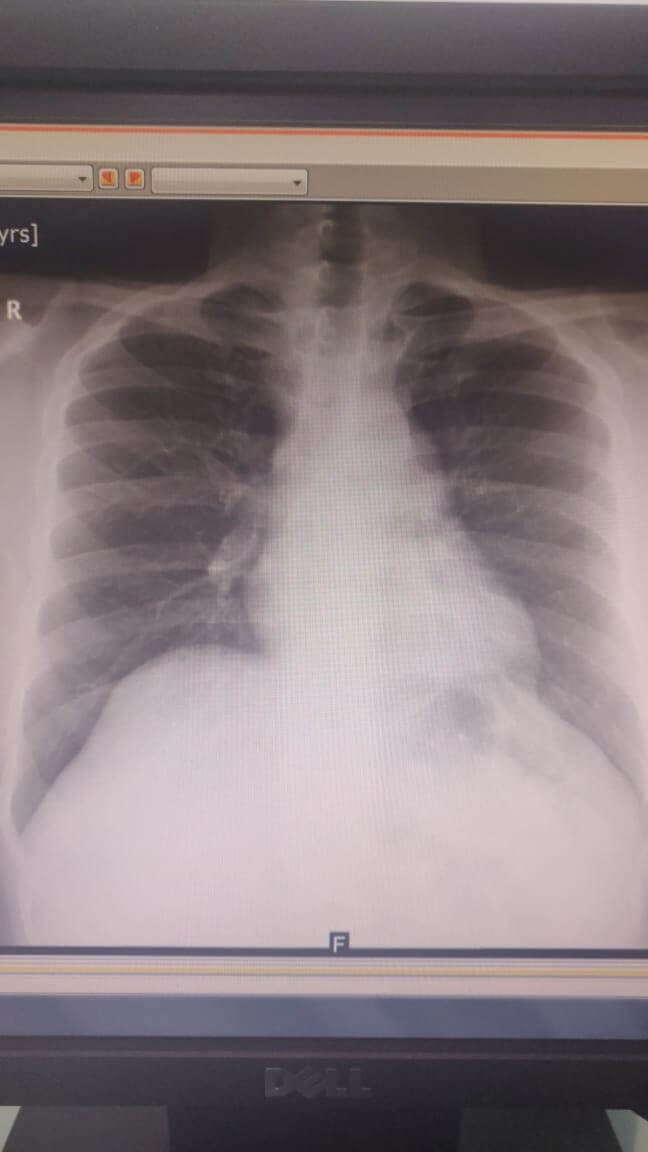

পেশাগত স্ক্রীনিংয়ের সময় একজন 31 বছর বয়সী পুরুষ রোগীর বাম মিডিয়াস্টিনাল ভরের আনুষঙ্গিক অনুসন্ধান ছিল।

রোগীর সিটিতে সিস্টিক ভর দেখা গেছে। রোবোটিক বাম মিডিয়াস্টিনাল টিউমার ছেদনের পরিকল্পনা করা হয়েছিল। টেবিলে, সিস্টিক ভর পেরিকার্ডিয়াল সিস্ট হিসাবে নিশ্চিত করা হয়েছিল এবং এক্সাইজ করা হয়েছিল। অপারেশনের পর দ্বিতীয় দিনে রোগীকে ছেড়ে দেওয়া হয় এবং এক সপ্তাহের মধ্যে আবার কাজ শুরু করে।